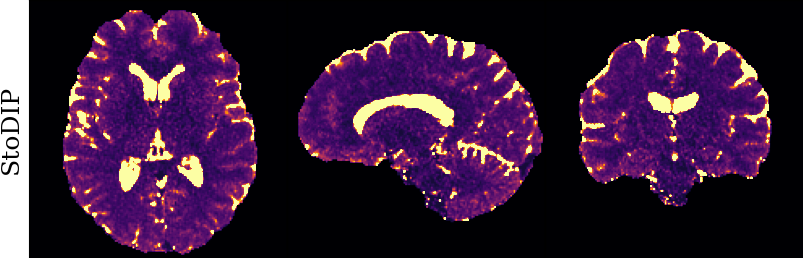

To monitor performance progress, we mapped TSMI to Q-Maps every five epochs. To mitigate the lengthy processing times associated with Dictionary Matching, we implemented a fully connected network to directly map TSMI to Q-Maps [5], significantly reducing processing time. However, for the final assessment, we employed DM on all techniques at the conclusion of the training process (epoch 500). We report in Table 1 the Mean Average Percentage Error (MAPE) of T1/T2 maps, and Peak Signal-to-Noise Ratio (PSNR) and Structural Similarity (SSIM) Index for T1/T2 and normalised PD. To accompany these metrics we also offer in Fig. 2 the reconstructed T1 and T2 maps for the different approaches.

The training and validation loss (Fig. 1) served as valuable guides for architecture and training design. To demonstrate this, we selected a subset of experiments in which we kept certain variables fixed and only modified the one under inspection. From Fig. 1 (a)-(d), MAPEs curves show there is a clear setting with the preferred performance. Specifically, from Fig. 1a, it is evident that using DRUNet yields a clear improvement over the original architecture. This could be attributed to the utilisation of residual units in addition to other architecture differences, such as the choice of upsampling operator (transpose convolution for DRUNet and trilinear for DIP). The choice of input (Fig. 1b) demonstrated a consistent pattern among the tested options, with low rank (conjugate gradient) initialiser marginally outperforming the others. Fig. 1cshows that by epoch 100, stochastic approaches exhibit lower reconstruction errors compared to non-stochastic methods. For example, adaptive LR with stochastic training yields a combined MAPE of 61.40% (17.09% T1 and 44.31% T2) vs. 213.69% (35.50% T1 and 178.19% T2) for the non-stochastic method. This fast convergence is due to adaptive LR and stochastic updates across coils. Despite similar execution times ( 34 min for stochastic with adaptive LR vs. 32 min for non-stochastic with fixed LR), the rapid error reduction makes StoDIP more attractive for training.. To assess the early stopping of DIP models, a key element, we present Fig. 1d. The original work by Ulyanov et al. [21] used 2k iterations, while Hamilton et al. [12] used 30k. In contrast, our settings show StoDIP achieving competitive performance in under 500 epochs (4k iterations) on the entire volume. However, StoDIP can overfit to k-space measurements, affecting reconstruction accuracy, and thus the iteration at which it stops could have a greater impact. We show that adding a spatial penalty term addresses overfitting and instabilities. This is supported by the maps in Fig.2, supplementary material Figures 1-3, and metrics in Table 1. StoDIP reconstructions lack aliasing artifacts, and the TV regularizer (StoDIP + TV) further improves Q-Map reconstruction by reducing checkerboard artifacts observed in StoDIP outputs alone.